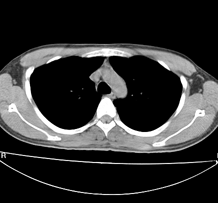

左肺上叶尖后段胸膜下可见两个类圆形薄壁空洞,内外壁较光滑,腔内为气体密度,支持结核性薄壁空洞。

临床无症状,左上肺两枚厚壁空洞,内无气液平面,周围未见卫星灶,囊肿可能大,建议追问病史。请各位老师指正

左飞上叶尖后段两个含气的囊性肿块,边界清晰,其周围未见卫星病灶,考虑肺囊肿.不支持肺结核是因为未见卫星灶,临床未见体征.

左肺上叶后段见两个孤立圆形厚壁空洞,无液平及壁结节。周围清晰,无卫星灶。结合病史,如此大的病灶病人毫无感觉,另外周围如此清晰,应能排除结核空洞;肺囊肿壁应更薄,如合并感染可增厚,但周围应模糊。本人考虑:肺韦格肉芽肿。

左上叶尖后段可见两个中等壁厚空洞,腔内无液平,内外壁光整,局部轻度胸膜增厚,首虑结核。

肺囊肿多见于中下肺,上肺少见,且壁薄。该例有卫星灶更象结核空洞。

左肺尖后段的两个薄壁(纵隔窗)含气囊样病变,壁厚薄较均匀、光整、内无液气平形成、其邻近肺野见

少许渗出、未见卫星灶,其余肺野未见明显支气管播散灶(楼主虽然未上传全其他层面图片,但认为因正常而未上传)。

综合上述:考虑为肺囊肿合并感染,不支持结核空洞(虽然病变位于结核好发区,但认为这么明显的结核空洞应该有明显的肺内支气管播散灶)。